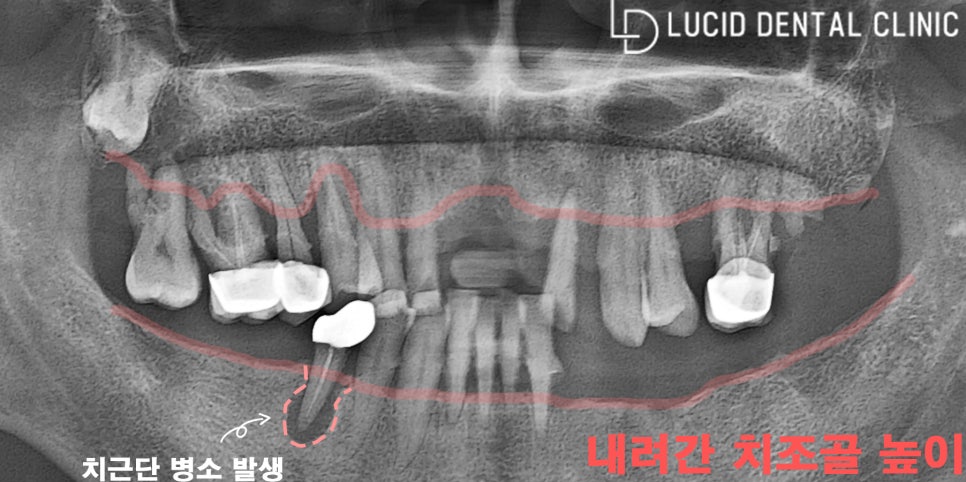

지금 보는 건 파노라마 방사선 사진인데요.

현재 하악(아래턱) 구치부(어금니)가 모두 발거됐고,

신경치료를 받은 곳은 치근단 병소가 나타났습니다.

그뿐만 아니라 상악(위턱)치아가 대부분 정출되어

제대로 된 곳에 위치하지 못하고 있었는데요.

이런 상태로는 올바른 교합이 이루어지지 않아

저작 기능에도 굉장히 불편했을 것으로 보입니다.